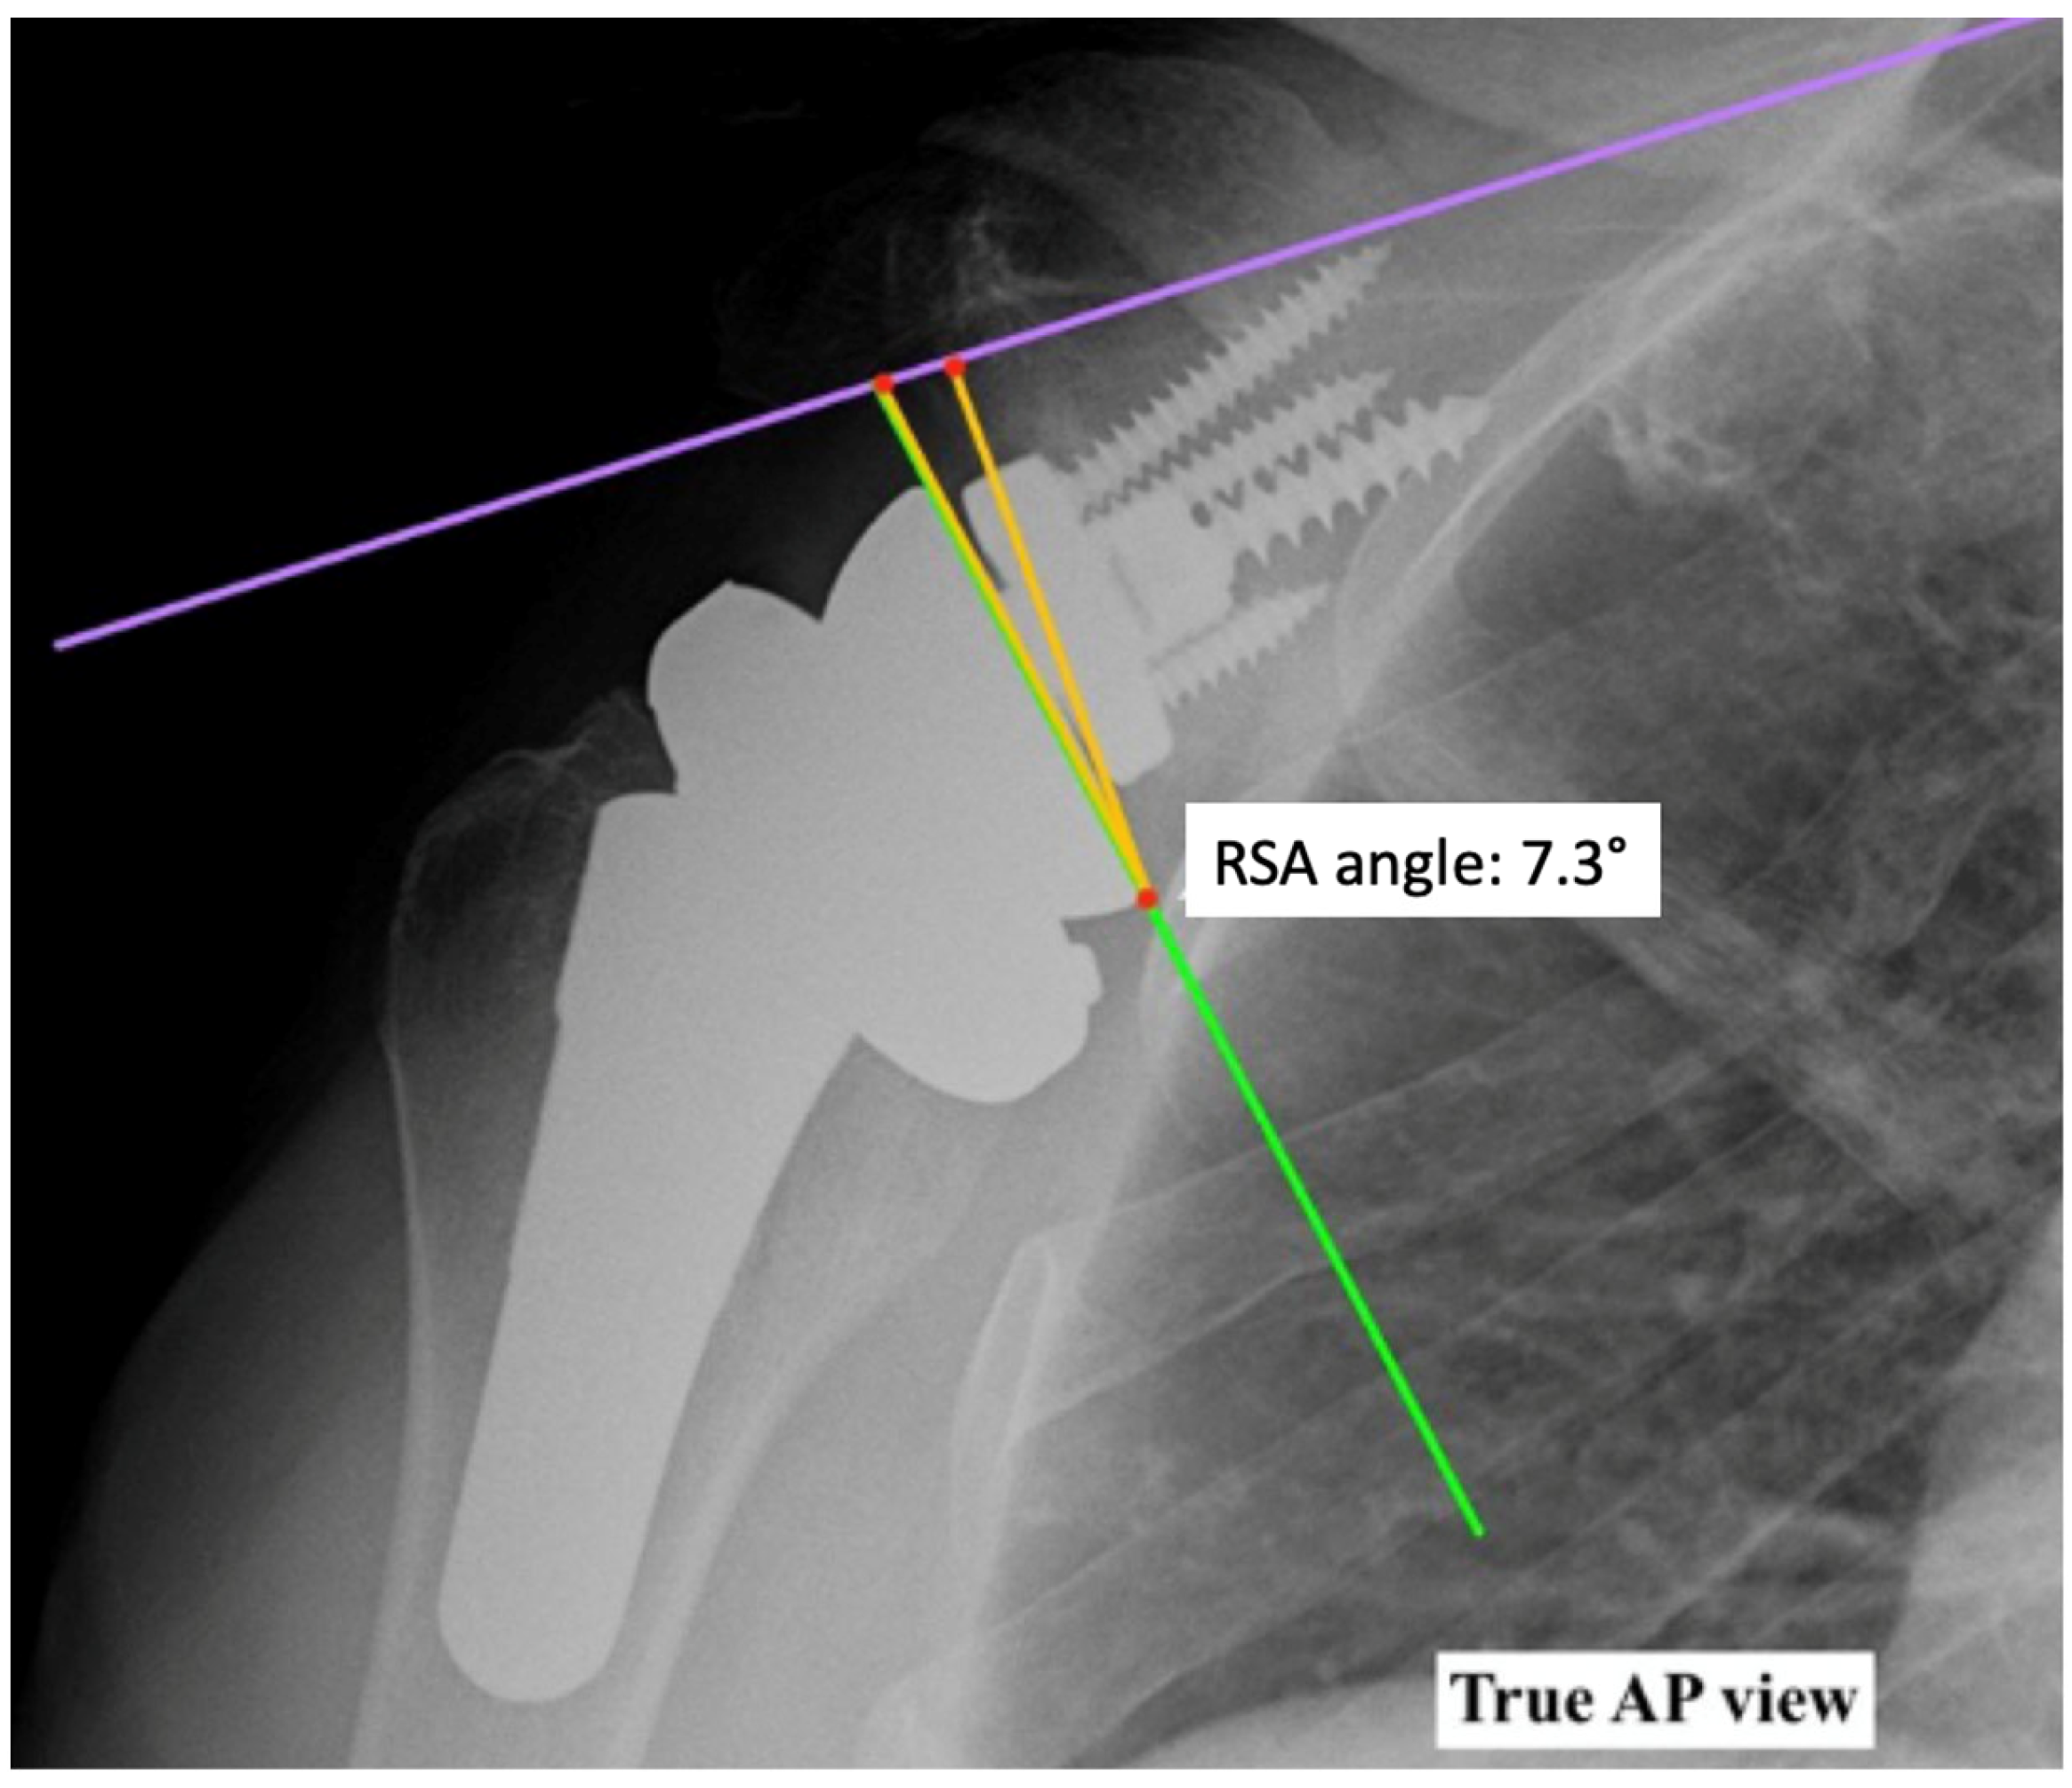

4. Radiographic Evaluation of Grammont-Style Reverse Arthroplasty

- Boileau, P.; Gauci, M.-O.; Wagner, E.R.; Clowez, G.; Chaoui, J.; Chelli, M.; Walch, G. The Reverse Shoulder Arthroplasty Angle: A New Measurement of Glenoid Inclination for Reverse Shoulder Arthroplasty. J. Shoulder Elb. Surg. 2019, 28, 1281–1290. [Google Scholar] [CrossRef] [PubMed]

- Werthel, J.-D.; Villard, A.; Kazum, E.; Deransart, P.; Ramirez, O. Accuracy of Reverse Shoulder Arthroplasty Angle According to the Size of the Baseplate. J. Shoulder Elb. Surg. 2023, 32, 310–317. [Google Scholar] [CrossRef] [PubMed]

- Falaise, V.; Levigne, C.; Favard, L. Scapular Notching in Reverse Shoulder Arthroplasties: The Influence of Glenometaphyseal Angle. Orthop. Traumatol. Surg. Res. 2011, 97, S131–S137. [Google Scholar] [CrossRef] [PubMed]

- Gutiérrez, S.; Walker, M.; Willis, M.; Pupello, D.R.; Frankle, M.A. Effects of Tilt and Glenosphere Eccentricity on Baseplate/Bone Interface Forces in a Computational Model, Validated by a Mechanical Model, of Reverse Shoulder Arthroplasty. J. Shoulder Elb. Surg. 2011, 20, 732–739. [Google Scholar] [CrossRef]

- Laver, L.; Garrigues, G.E. Avoiding Superior Tilt in Reverse Shoulder Arthroplasty: A Review of the Literature and Technical Recommendations. J. Shoulder Elb. Surg. 2014, 23, 1582–1590. [Google Scholar] [CrossRef] [PubMed]